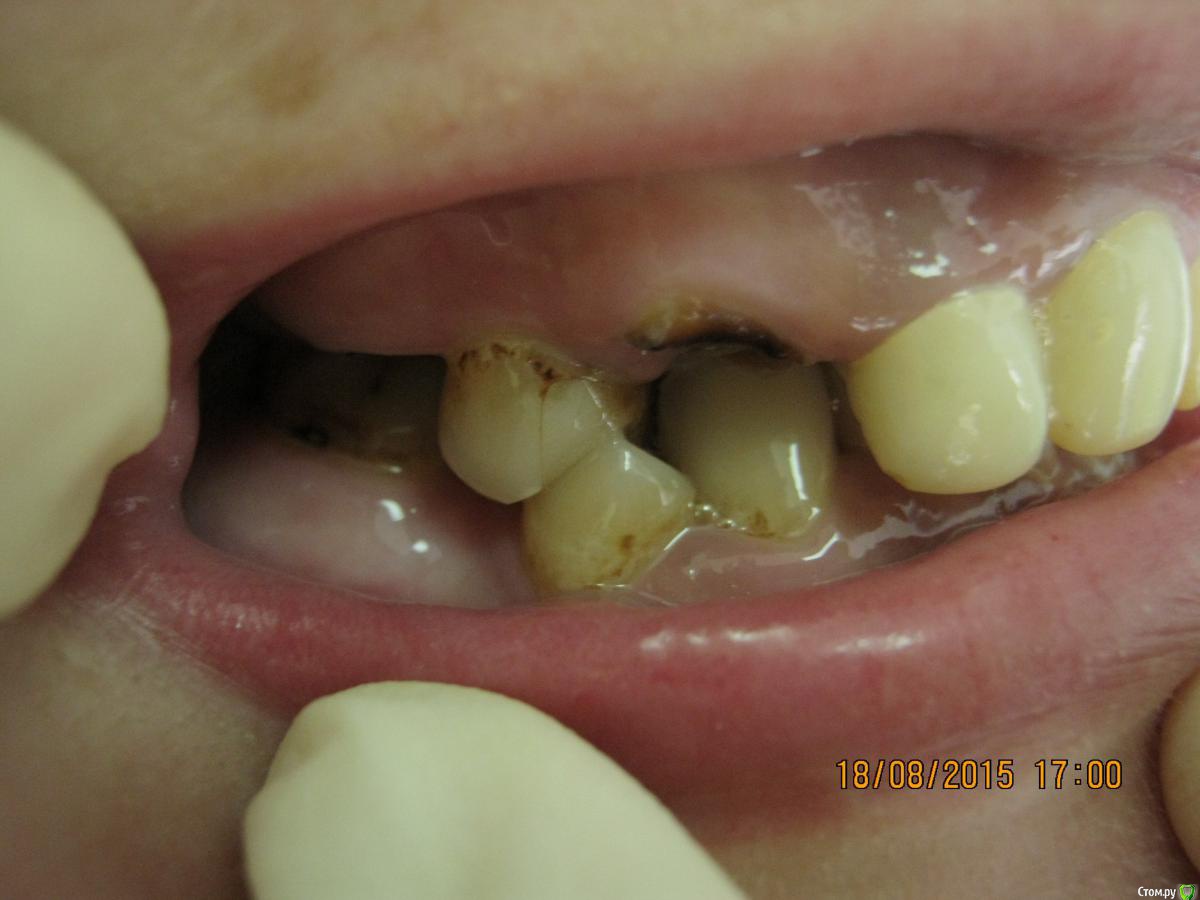

SeregaStomatolog Опубликовано 18 августа, 2015 Поделиться Опубликовано 18 августа, 2015 Добрый вечер уважаемые коллеги!В клинику обратилась пациентка с такой ситуацией во рту.Подскажите пожалуйста что можно сделать и с чего начать. Ссылка на комментарий

SeregaStomatolog Опубликовано 18 августа, 2015 Автор Поделиться Опубликовано 18 августа, 2015 Во-первых она хочет нормально улыбаться,не стесняясь отсутствующего клыка.Во-вторых она хочет нормально жевать,т.к. отсутствие 1.7,1.6 не позволяет это делать.Я сразу сказал пациентке что вариантов без ортодонтии мало (если они вообще есть) и обещать ничего не стал.Случай сложный,поэтому хочется узнать в принципе,на будущее,какие варианты лечения возможны (если можно по подробнее).Пока что я снял слепки,отлил модели-пошел за советом к коллегам в другую клинику-все настаивают на ортодонтии.Теперь вся надежда на Вас коллеги,подскажите что можно придумать более менее приемлемое без ортодонтии. Ссылка на комментарий

SeregaStomatolog Опубликовано 18 августа, 2015 Автор Поделиться Опубликовано 18 августа, 2015 Сделав как хочет пациентка вы не получите красивый результат, которого она ждет! и получится что вы не смогли реализовать ее мечты , а значит доктор неахти)) да и вы не особо результатом будете довольны, вам это надо? Если в эстетике проблем нет, восстановите функцию. Ненужное удалить, длинные зубы дэпульпировать, укоротить ну и коронуйте))Мне кажется если я возьмусь,то все равно не буду результатом доволен,т.к. все реализовать не получится.Самая большая проблема в области отсутствующих 1.6,1.7-зубо-альвеолярное удлинение 4.6,4.7 настолько велико,что они практически касаются слизистой в области 1.6,1.7. Ссылка на комментарий